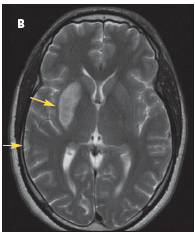

The patient was admitted with a diagnosis of stroke. A CT scan of the brain revealed no bleeding or infarction. A CT angiogram showed bilateral internal carotid dissection, on the right more than the left (A). A heparin drip and aspirin were started. MRI done 24 hours later showed acute infarction in the right basal ganglia and to a smaller degree in the right temporal lobe (B); petechial hemorrhages were noted in the acute infarction. At this point, the heparin drip and aspirin were discontinued. The patient could not be anticoagulated because of the hemorrhagic conversion.